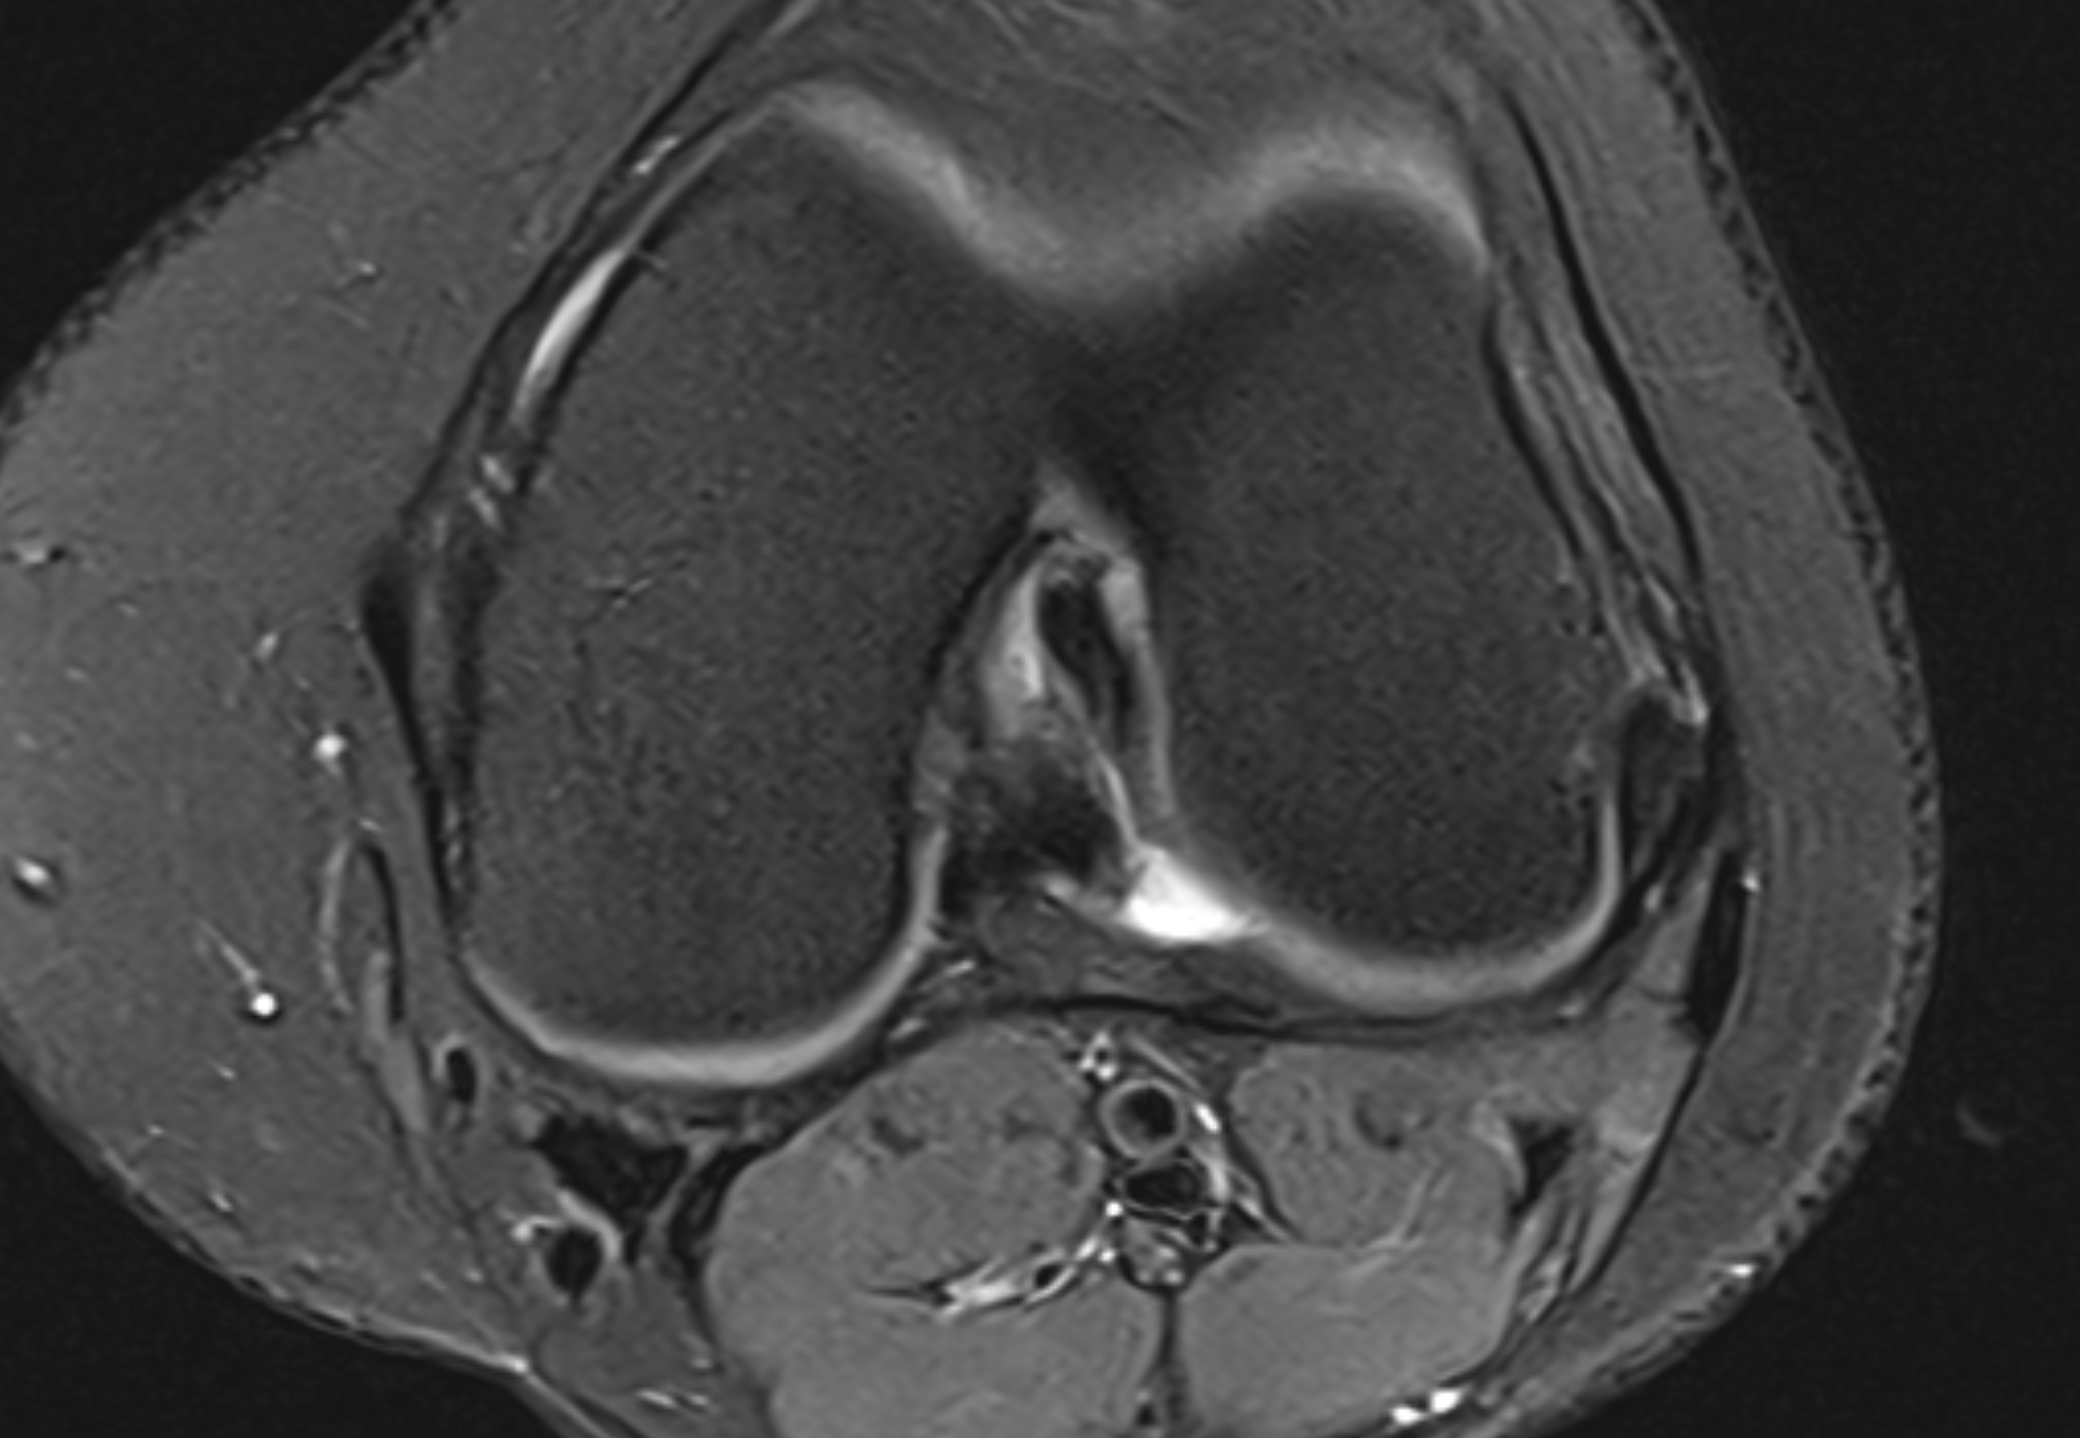

The Double PCL Sign

View: Sagittal (Midline)

Double PCL Sign

What the marker shows: The native Posterior Cruciate Ligament (PCL) is the top dark band. The red marker highlights the second band resting directly beneath it.

This lower band is the torn inner rim of the meniscus that has migrated into the center of the knee joint.